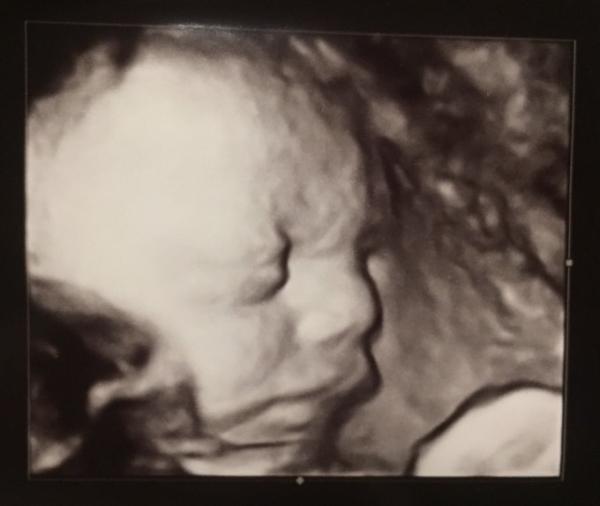

Hallo ihr Lieben, ich hatte heute auch das 3.Screening und möchte euch gerne davon berichten. Krümelchen liegt aktuell startklar, mal sehen wie lange Den Oberschenkelknochen hat sie 2x gemessen, kam aber immer auf den selben recht hohen Wert Damit kommt er auf ein stattliches Gewicht von etwa 1800g kleiner Mops Und ca. 43 cm...aber es sind ja noch 9 Wochen Meine FÄ war sonst sehr zufrieden, alles fein mit dem Kleinen. Bei dem 3D-Bild hat sie sich richtig abgemüht und es insgesamt 5x während den Messungen probiert, bis wir 2 schöne Bilder hatten Es war nämlich das allererste und ich muss das extra zahlen, bzw. kann es dann später bei meiner KK abrechnen. Was soll ich sagen, er ist perfekt Meine Niere ist leider unverändert gestaut, aber ich habe keine Beschwerden...so lange wird also auch nix unternommen. Den gelben Schein für AG und Krankenkasse bzgl. des mutmaßlichen ET gab’s heute auch schon. In 2 Wo gibt’s wieder CTG und die Niere wird kontrolliert. Ich muss jetzt also alle 2 Wochen zur FÄ. Ich wünsche euch noch einen schönen Abend

Bild zu 3. Screening - Forum für Januar - Mamis